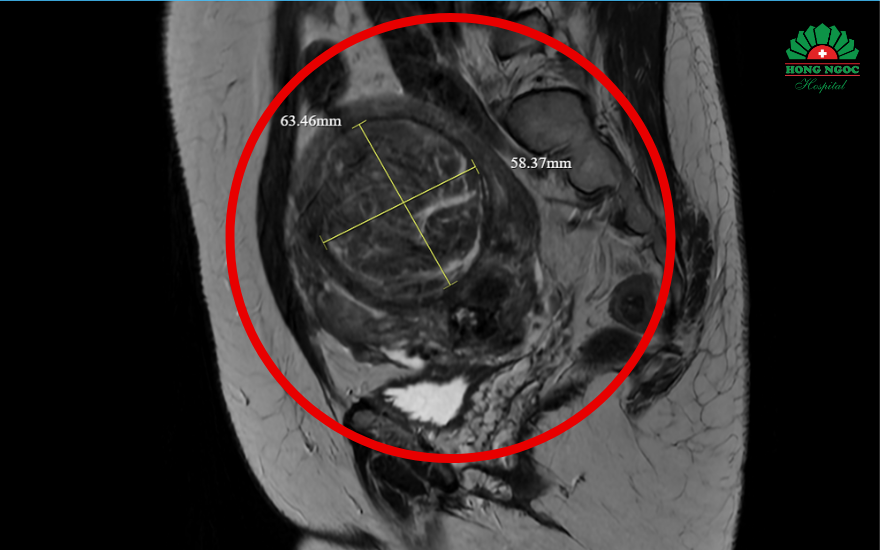

Kết quả kiểm tra tại BVĐK Hồng Ngọc cho thấy, chị Hà có tử cung to bất thường, kích thước tương đương thai 6 tháng với nhiều u xơ tử cung, khối lớn nhất 7cm. "Khi tiếp nhận, người bệnh ở trong tình trạng xanh xao, niêm mạc nhợt nhạt - triệu chứng điển hình của tình trạng thiếu máu do rong kinh. Hình ảnh siêu âm và chụp cộng hưởng từ cho thấy các khối u xơ chèn ép vào nhiều cơ quan, đặc biệt là bàng quang và trực tràng dẫn đến tình trạng căng tức khó chịu". THS.BS Đỗ Huy Hoàng (Khoa Chẩn đoán hình ảnh và Điện quang can thiệp, Bệnh viện Đa khoa Hồng Ngọc - Phúc Trường Minh) cho hay.

Hình ảnh siêu âm cho thấy nhiều u xơ tử cung, trong đó khối lớn nhất gần 7cm.

Hình ảnh khối u trước và sau khi nút mạch: toàn bộ mạch máu được nút tắc thành công.